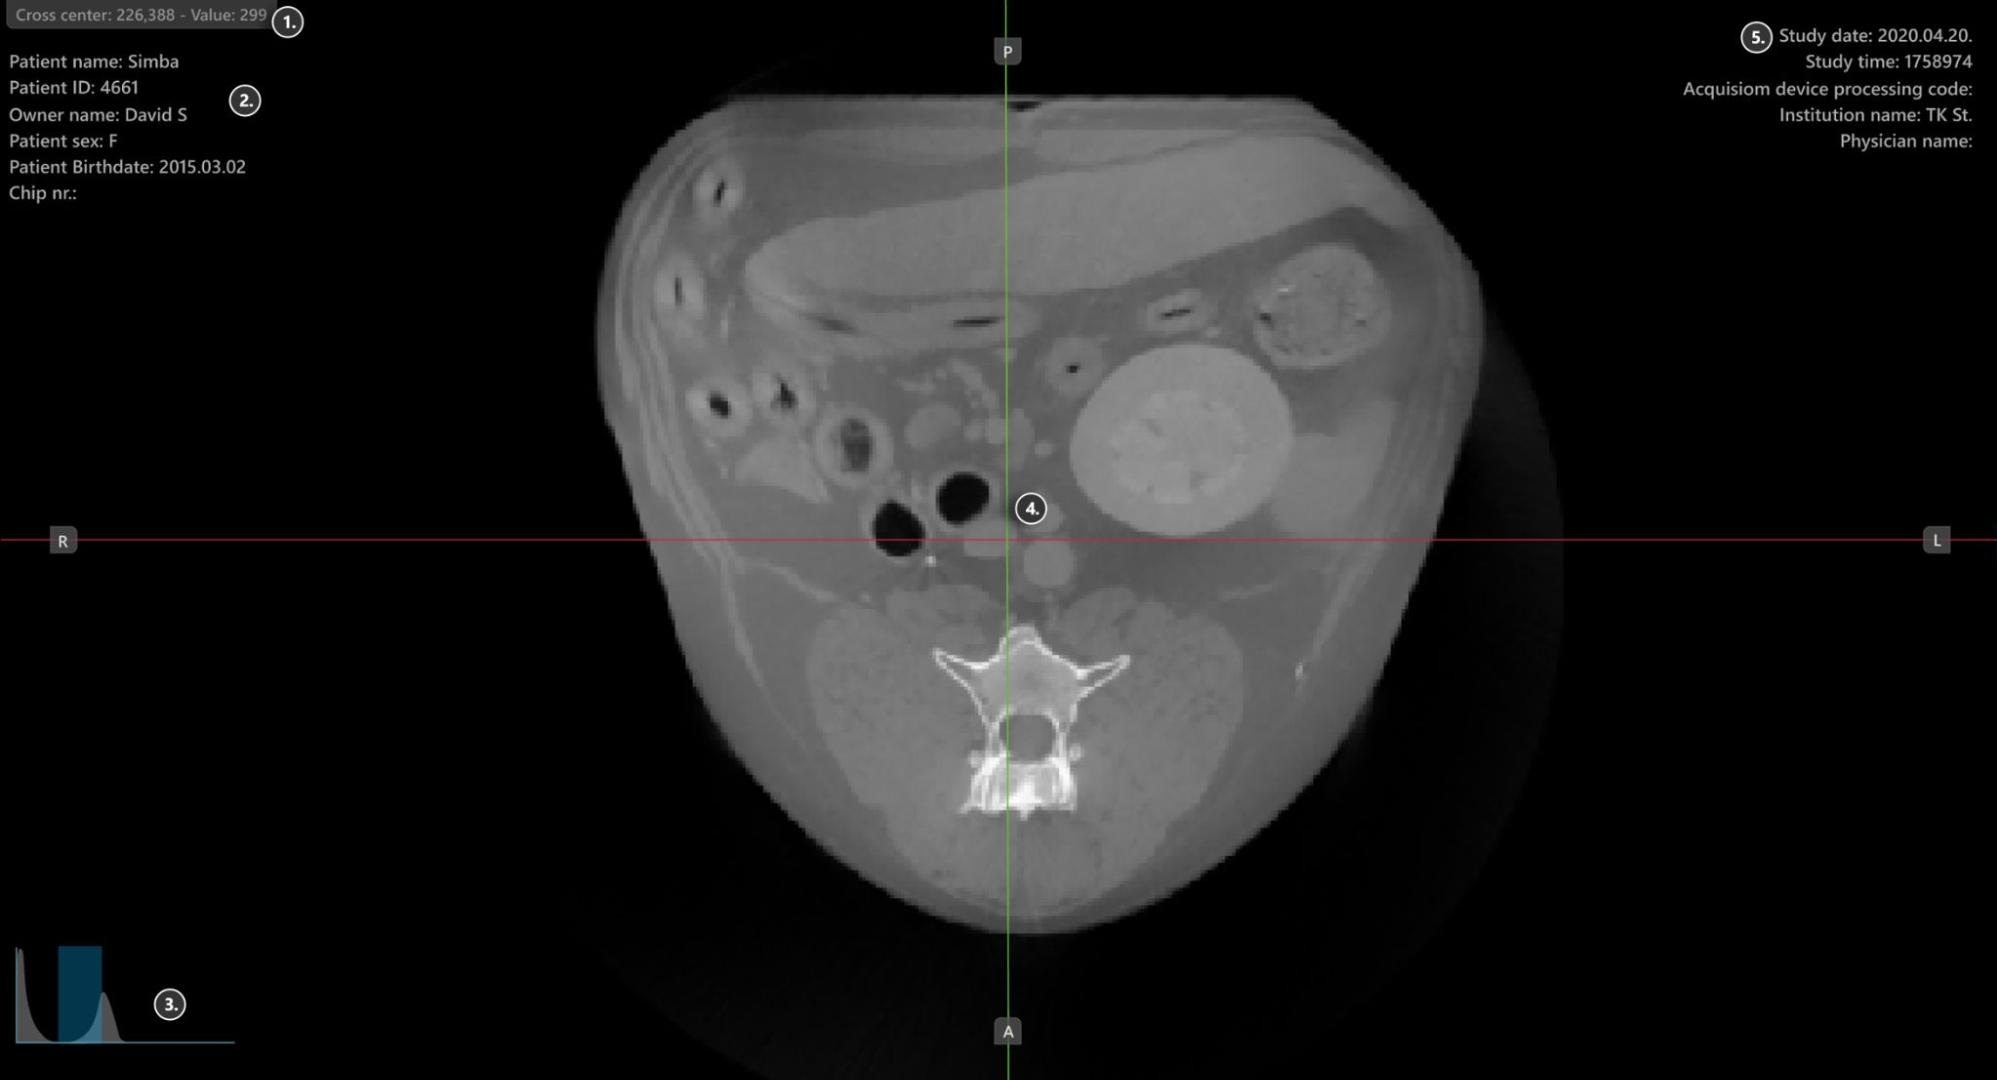

Sections of the VisioVIEW CT Viewer¶

The VisioVIEW CT Viewer consists of several sections, each tailored to a specific purpose. Below is a detailed description of each section.

Viewer Area¶

HU (Hounsfield Unit) pixel value

Patient information

Windowing histogram tool

Slicers

Study information